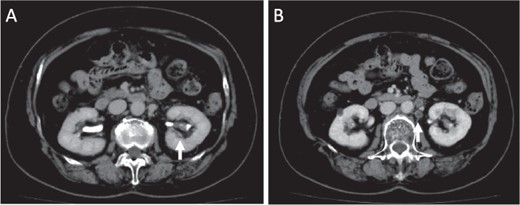

Microscopical photographs of the tumor stained by alcian blue staining and immunohistochemistry of the tumor and the metastatic lesion of the lymph node. The microscopical photographs of tumor with alcian blue staining (A), immunohistochemical staining of AMACR (B) and E-cadherin (C) are shown. A microscopical photograph of lymph node-metastasis of the tumor is also shown (D). Original magnification of the objective lens of A, B, C and D is ×10, ×10, ×10 and ×4, respectively.

Initially, chemotherapy using gemcitabine (1300 mg/body) plus cisplatin (94 mg/day) was started 1 month after her initial visit, resulting in progressive disease. Subsequently, methotrexate, vinblastine, adriamycin and cisplatin therapies (methotrexate, 30–39 mg/body/day; vinblastine, 3.0–3.9 mg/body/day; Adriamycin, 30–39 mg/body/kg; cisplatin, 70–92 mg/body/day) were started. A total of four courses of the therapy were performed, with no effect on the tumor size. Therefore, nephrectomy of her left kidney and dissection of the regional lymph nodes were performed 8 months after her initial visit to the hospital. As shown in Fig. 2, the tumor was observed in the lower part of the pelvis to the parenchyma of the left kidney during macroscopic examination. The tumor size was 35 × 25 × 20 mm, and the color of the tumor was whitish yellow (Fig. 2). Histologically, the tumor consisted of elongated tubular structure and spindle cells with mucinous stroma (Fig. 3A and B). The spindle cell showed enlarged nuclei and prominent nucleoli, suggesting Fuhrman grade 4 (Fig. 3C). Partially, macrophages were prominent in the tumor (Fig. 3D). Alcina blue-positive mucin was also observed in the stroma of the tumor (Fig. 4A). Although the tumor projected to the renal pelvis, the tumor was lined with normal urothelial cells.

Immunohistochemically, the tumor was positive for α-methyl acyl CoA racemase (AMACR), cluster of differentiation (CD) 10, renal cell carcinoma marker (RCC-Ma) and carbonic anhydrase 9 (Fig. 4B and data not shown). The tumor was partially positive for E-cadherin (Fig. 4C). The tumor was negative for cytokeratin (CK) 7, CK20 and CK AE1/AE3 (data not shown) and invaded the vein and metastasized into the regional lymph nodes (11/17) (Fig. 4D). Based on the morphological feature and immunohistochemical staining, the tumor was diagnosed as high-grade MTSCC with regional lymph node metastasis. Administration of pazopanib (600 mg/day) was started 4 months after the operation. Medication was switched from pazopanib to axitinib (10 mg/day) 6 months after the operation. Fifteen months after the operation, metastases in the lung and supraclavicular lymph nodes were observed by CT scan with local recurrence of the tumor. Two years after the operation, bone metastasis of the tumor was also observed. After approximately 2 years and 1 month after nephrectomy, she is still alive but still experiencing tumor metastasis and recurrence.